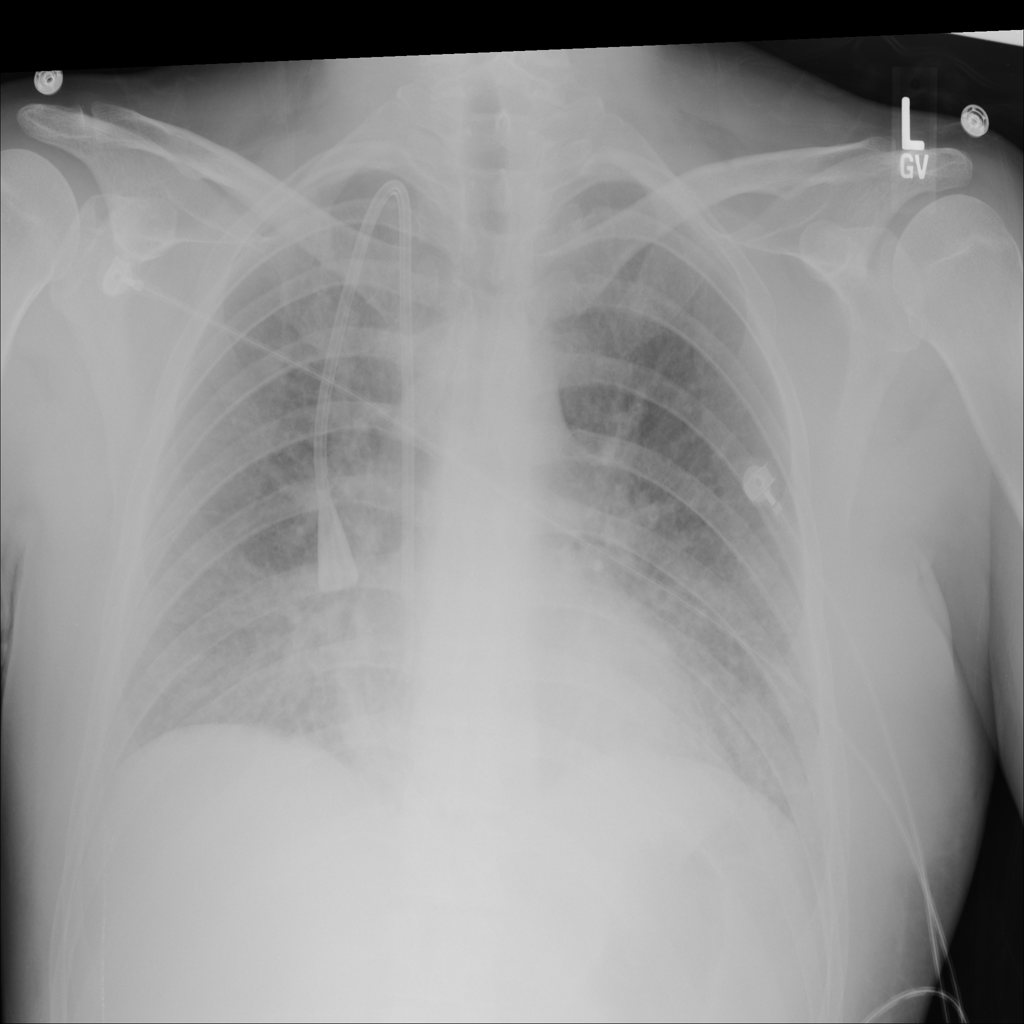

PAT-24D9 · IMG-006Edema

PAT-24D9 · IMG-006

AP